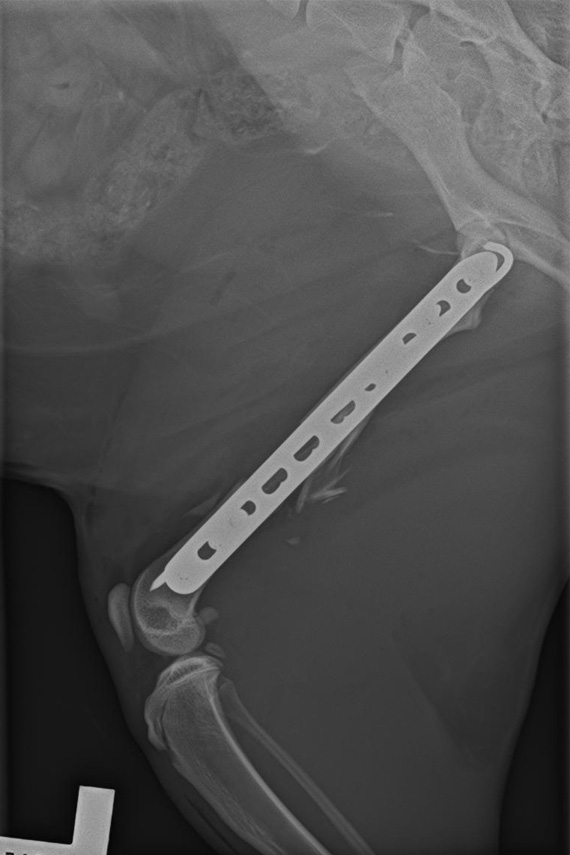

Versorgung Femurfraktur

Versorgung der Femurtrümmerfraktur der Katze aus Abb. 1 mit Platte und IM Nagel (Plate and Rod).

Seitliches Kontrollröntgen nach Versorgung Femurfraktur

Seitliches Kontrollröntgen: eine sehr stabile Versorgung dieser sehr instabilen Fraktur.